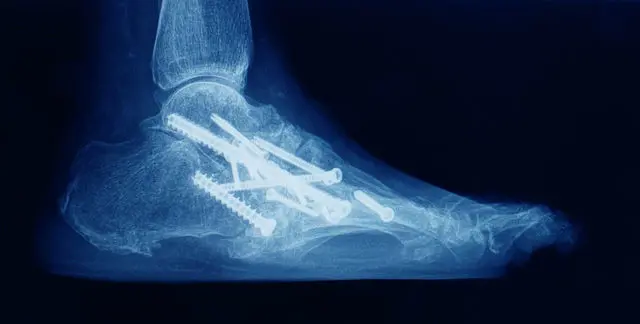

Fixation options

Multiple large-diameter screws (often 2-3)

Plate + screws constructs (especially anterior plating)

Hybrid screw + plate designs

Supplemental external fixation in challenging cases

Bone grafting (autograft / allograft / bone substitutes) where defects exist

Bone Alignment: The tibia and talus bones are positioned in a natural alignment.

Fixation: Screws, plates, or rods are used to hold the bones together.